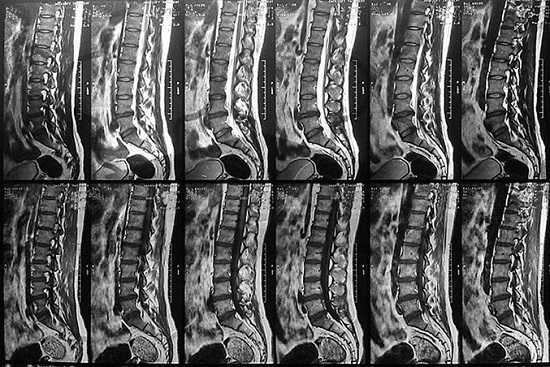

Пленка с серией снимков пояснично-крестцового отдела позвоночника в сагиттальной проекции